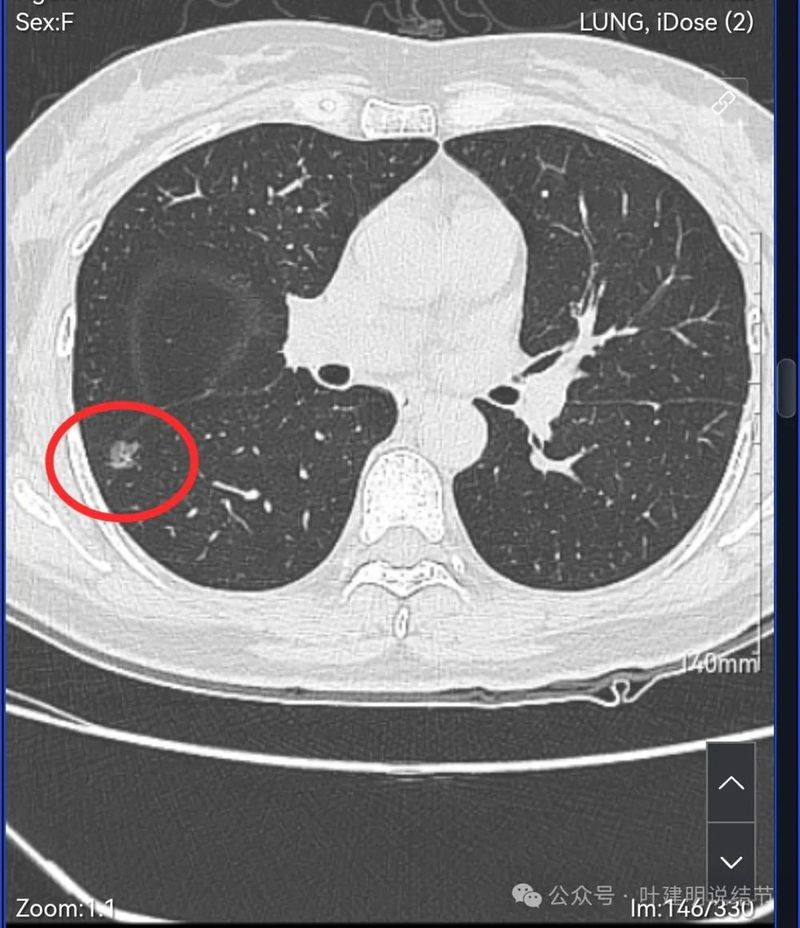

密度不太纯,轮廓与边界清。

表面分叶,中间空泡,边缘有磨玻璃成分,叶间胸膜凹陷。

灶内血管穿行,表面分叶、中间空泡,实性成分。

血管进入,表面分叶,密度不均。

密度显杂乱,血管贴边。

细毛刺或小棘突,表面不平。

边缘区磨玻璃密度,有微小血管贴着。

像今天分享的这种磨玻璃结节,是不能再随访的。由于:1、密度不纯有实性成分;2、紧贴叶间裂(胸膜)而且贴胸膜侧密度较高;3、有血管进入与穿行且病灶内部密度显得较杂乱;4、随访过无好转。当然这样的病灶不是说再随访肯定要转移了,要失去手术机会或预后会不同,但这种有风险的磨玻璃结节,继续随访一是等不了多久还要再进展仍得短期内接受手术,这种短时间的创伤延迟没有多少价值,却要承担风险;二是这种边缘部分能楔形切除的病灶,手术本向创伤小、恢复快、肺功能损失不多,切了它是利大于弊的。只是本例来讲,已经进去了,病灶2与病灶1也应该考虑同期予以解决。我的想法是上叶的定位下大点的楔形切除或后段切除,下叶的只需切缘阴性少许肺组织楔切就可以,淋巴结采样与否关系都不大的。